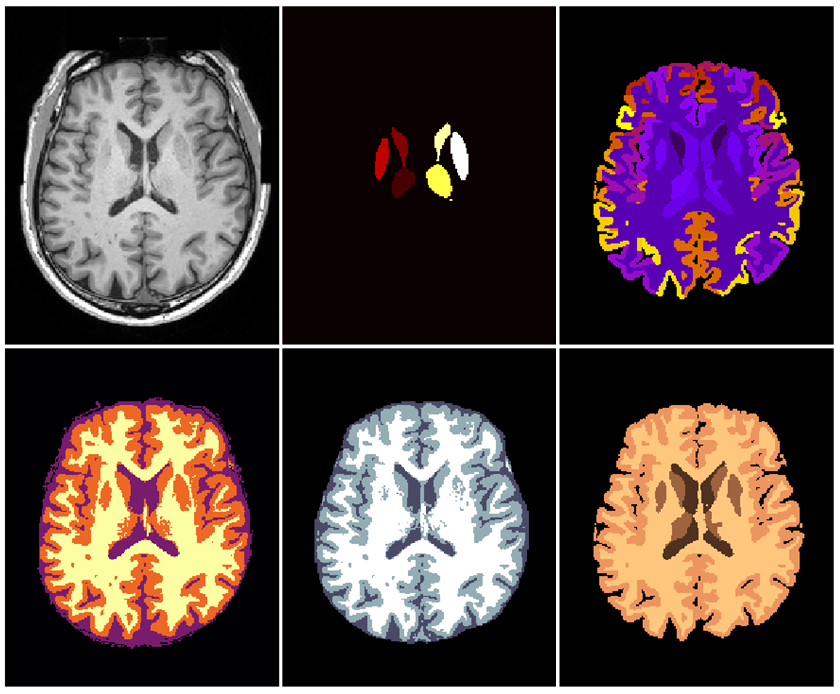

Refer to caption

Figure 4: Random NeuroNet (nn_all) segmentation example. From left to right: raw T1w input image, fsl_first, malp_em, spm_tissue, fsl_fast, malp_em_tissue.

Numerical accuracy results on compared network types single, nn_tissue and nn_all can be found in Tab. 1, 2 and 3, respectively. Using the multi-output architectures nn_tissue and nn_all yielded slightly reduced mean DSC over training several single networks. However, all numerical accuracy results are close for all compared network types. Fig. 5 summarises Tab. 1, 2 and 3 graphically. A randomly picked test image and the corresponding nn_all prediction is depicted in Figure 4.